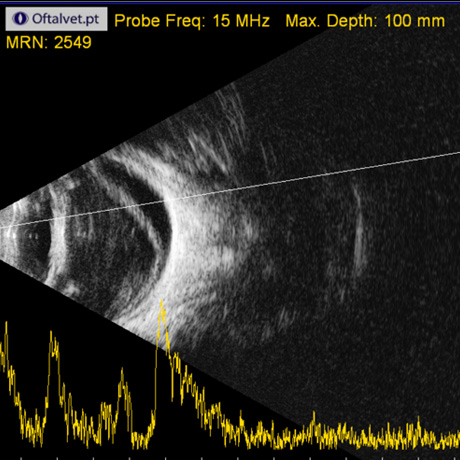

Na Oftalvet dispomos de equipamento avançado, de última geração, que permitem o diagnóstico das mais variadas doenças que afectam o globo ocular e seus anexos.